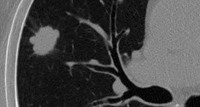

Часто доброкачественные опухоли легких являются случайными рентгенологическими находками, обнаруживаемыми при флюорографии. При рентгенографии легких доброкачественные опухоли легких определяются как округлые тени с четкими контурами различной величины. Их структура чаще однородная, иногда, однако, с плотными включениями: глыбчатыми обызвествлениями (гамартомы, туберкуломы), костными фрагментами (тератомы).

Детально оценить структуру доброкачественных опухолей легких позволяет компьютерная томография (КТ легких), определяющая не только плотные включения, но и наличие жировой ткани, свойственной липомам, жидкость - в опухолях сосудистого происхождения, дермоидных кистах. Метод компьютерной томографии с контрастным болюсным усилением позволяет дифференцировать доброкачественные опухоли легких с туберкуломами, периферическим раком, метастазами.